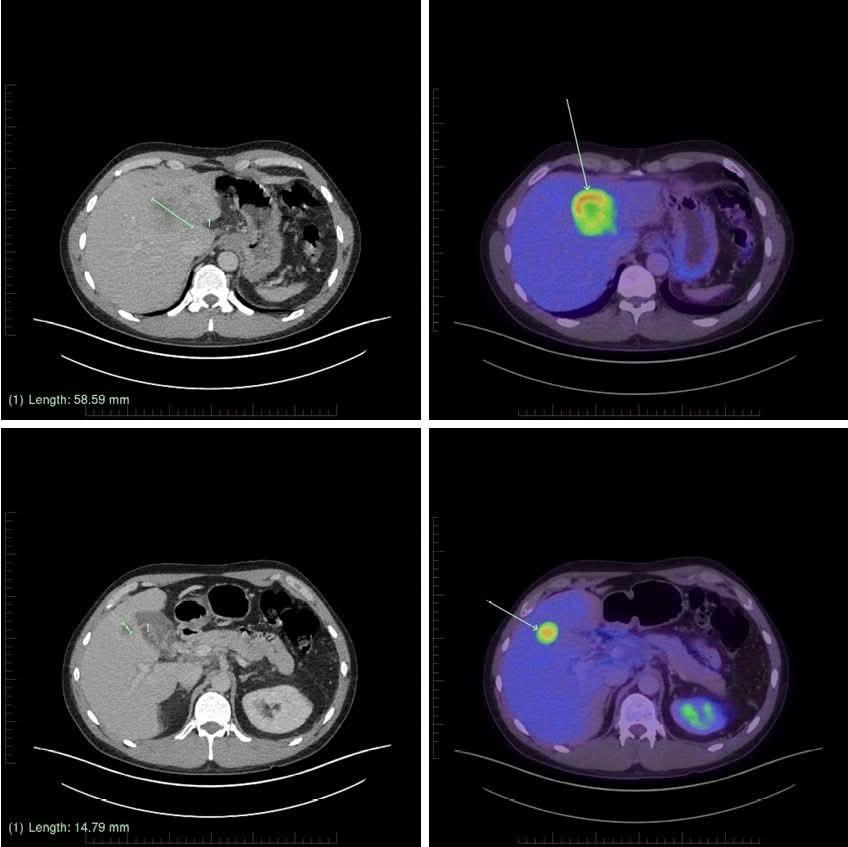

Had an Oncologist appointment to find out the results of my latest CT Scan, this was an urgent one done a few weeks back as liver function had started playing up)unfortunately looks like the Chemo im on isn't working anymore and the tumors are growing again, for example the biggest one went from 83mm to 58mm now back up to 74mm.